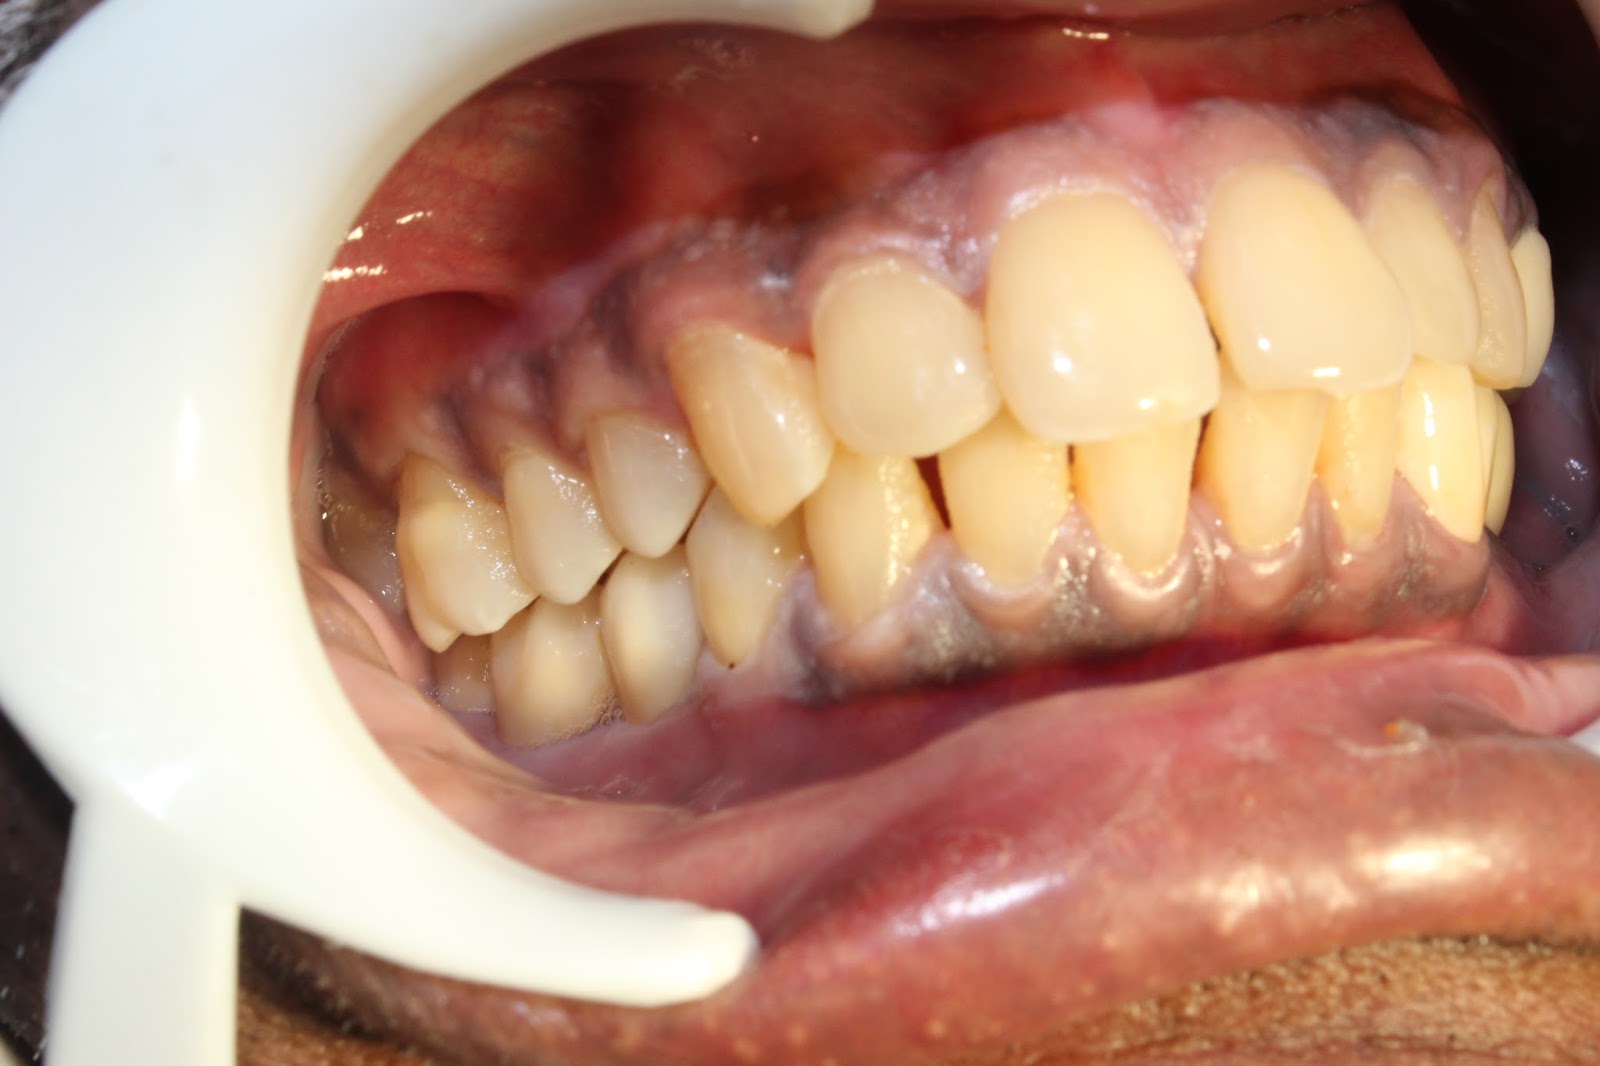

Zirconium bridges for teeth replacement with dental implants. Zirconium Dental Replacement dental crowns made of zirconia have many benefits, including strength and durability, but may not color match the rest of your teeth as well as porcelain. zirconia can be used to replace teeth that have been lost due to tooth decay, gum disease, or trauma. zirconia is a newer material for dental restorative treatments. It's a type. Zirconium Dental Replacement.

Zirconium bridges for teeth replacement with dental implants. Zirconium Dental Replacement It's a type of ceramic — or, in more specific terms, a. zirconia can be used to replace teeth that have been lost due to tooth decay, gum disease, or trauma. dental crowns made of zirconia have many benefits, including strength and durability, but may not color match the rest of your teeth as well as porcelain. . Zirconium Dental Replacement.